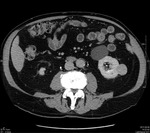

Proces zapalny obejmujący torbiel nerki może dać bardzo różnorodny obraz (zmiana charakteru płynu w obrębie torbieli znajduje odbicie w badaniach obrazowych). Obwodowe wzmocnienie pokontrastowe może wręcz potwierdzać występowanie ropnia.1 Tej koncepcji przeczy jednak stan kliniczny pacjenta i brak odchyleń od normy w badaniach laboratoryjnych. Rak nerkowokomórkowy przeważnie jest guzem o charakterze litym, jednak w ok. 20% przypadków może zawierać także elementy torbielowate.1 Obecność wzmocnienia obwodowego w fazie pokontrastowej badania TK, zwłaszcza rozmieszczonego nieregularnie, zawsze musi budzić podejrzenie rozrostu nowotworowego. U pacjenta, którego przypadek jest opisywany, na podstawie wyników badania histopatologicznego rozpoznano raka nerkowokomórkowego. Innym przykładem guza nowotworowego o charakterze torbielowatym, który może występować w obrębie nerki, jest torbielakogruczolak, znany także jako nerczak torbielowaty wielokomorowy. Guz najczęściej stwierdza się u małych chłopców i kobiet w wieku 40-70 lat (inaczej niż w prezentowanym przypadku). Składa się on z licznych torbieli wypełnionych śluzowatą treścią. W obrębie guza często występują zwapnienia (szacuje się, że w 10-50% przypadków), natomiast obszary krwotoczne lub martwicy, zazwyczaj obserwowane w rakach nerkowokomórkowych, w nerczakach torbielowatych są rzadkie. Kielichy i miedniczka nerki bywają modelowane przez torbiele, które nie komunikują się z układem wydalniczym. Po podaniu środka kontrastowego wzmocnieniu ulega lita część guza.1 Typowy obraz TK torbielakogruczolaka nerki zaprezentowano na rycinie 3A-C.